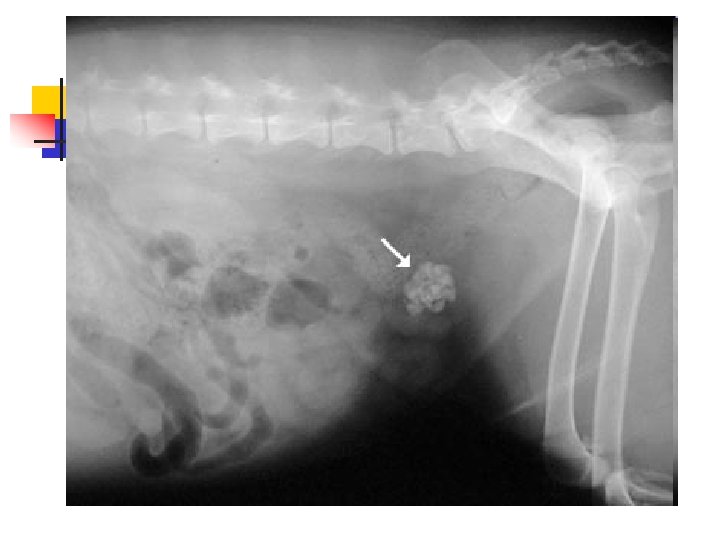

Bladder Stones n n n Bladder stones (also known as uroliths or cystic calculi) are hard, rock-like lumps of mineral that form in the urinary tract. Dogs and cats are different and usually form stones in the bladder. Because it is a bigger space, these stones tend to be much larger and usually cannot be passed, but have to be removed surgically or dissolved with special diets.

Bladder Stones n We suspect bladder stones when a dog has blood in the urine that doesn't respond to conventional antibiotic therapy, when we palpate a thickened bladder, when a dog strains to urinate, or when there are many crystals in a urine sample.

Bladder Stones n n Because most stones contain calcium, they are usually visible on a radiograph as white (bone density) objects in the area of the bladder. Sometimes there is a single large stone, and sometimes there are literally hundreds of tiny stones like sand or aquarium gravel.